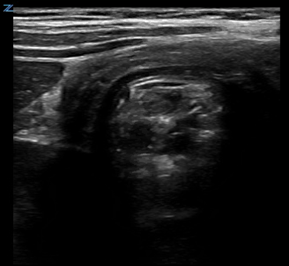

Classically, intussusception manifests in the transverse orientation as a ‘target sign’ or ‘donut sign’ (Figure 1) representing layers of intestine within the intestine. In the longitudinal orientation, the layers of intestine appear as a ‘pitchfork’ or ‘submarine sandwich’ (Figure 2). These findings are most commonly seen in the right lower quadrant for ileocolic intussusception, which is the most common type of intussusception. Small bowel intussusceptions can be differentiated by their size, which are often ≤3 cm.5 While small bowel intussusceptions often spontaneously reduce, if symptoms and findings persist, computed tomography (CT) may be necessary to determine management. POCUS is useful in differentiating variants of intussusception that range from a surgical emergency to a transient source of abdominal pain allowing clinicians to better manage these patients.6

Figure 1. Target Sign on cross-sectional image of intussusception